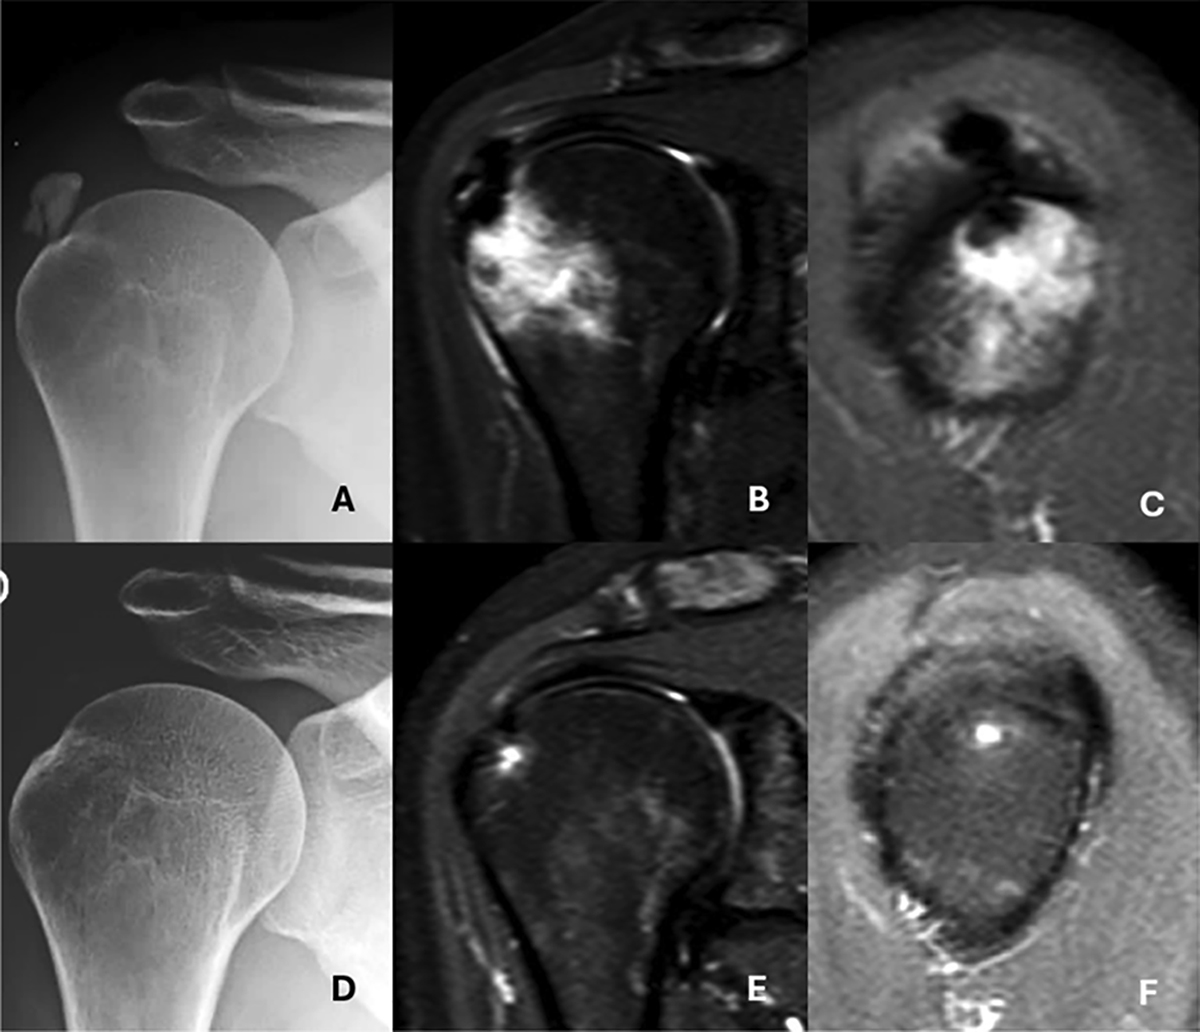

Figure 4

Advanced intraosseous migration (Type III-b) of a supraspinatus calcification with spontaneous resolution at follow-up. A. Initial anteroposterior (AP) radiograph showing the calcific deposit. B. Coronal MRI revealing intraosseous extension of the deposit with associated bone marrow edema. C. Oblique sagittal MRI demonstrating the “hourglass sign,” indicating tendon-to-bone continuity. D. Follow-up AP radiograph two years later showing complete disappearance of the calcification. E. Coronal MRI confirming resolution of the intraosseous deposit. F. Oblique sagittal MRI showing complete resolution of both the calcification and bone marrow edema.